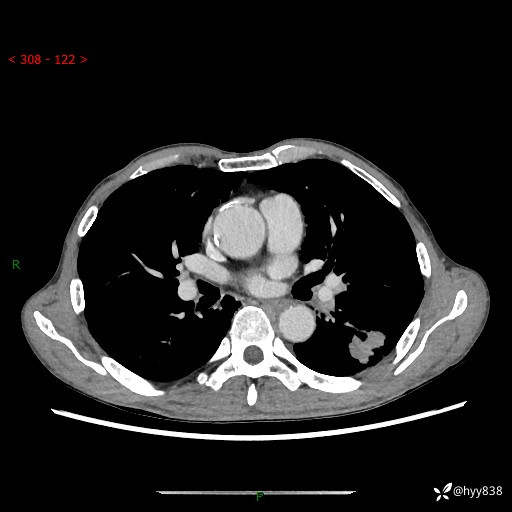

现病史:患者于1月余前无明显诱因出现背部疼痛不适,无明显咳嗽、咳痰、胸闷、咯血、发热等不适,后于2024.5.3至当地市人民医院行胸部CT示:左肺下叶结块,大小约2.2cm*2.6cm,双肺多发小结节,双肺感染性病变,部分纤维增值灶,慢支并双肺局限性肺气肿,肺大泡,纵隔淋巴结增大并部分钙化,冠脉区及大血管壁钙化,双侧胸膜局限性增厚;后口服莫西沙星2周。2024.6.12复查胸部CT示:左肺下叶结块影形态较前饱满,较大截面范围约2.8cm*2.3cm,边缘可见细短毛刺及分叶,性质待查。现患者为求进一步诊治来我院,门诊以“肺占位”收入我科。 起病来,患者精神、食欲、睡眠尚可,大小便正常,体力体重轻微下降。

胸部CT平扫+增强

各期CT值:48hu 100hu 78hu